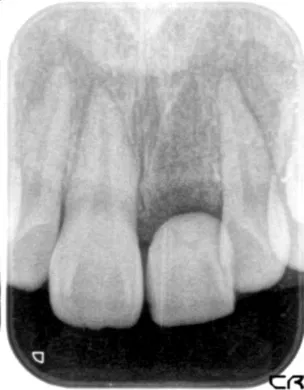

初診時

| 患者様のお悩み | 外傷で歯が抜けた |

|---|---|

| 治療法・使用素材 | インプラント治療の後、セラミック治療 |

| 患者様の年代 | 20代 |

| 治療開始年齢 | 20代 |

| 治療にかかった期間 | 8か月 |

| 性別 | 女性 |

| この治療のリスクについて | インプラントが正しい位置に入るかどうか |

| 治療にかかった費用 | 45万円 |